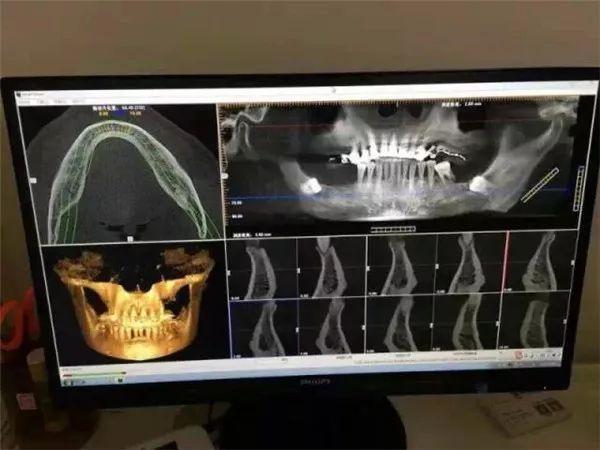

這臺堪稱口腔界“愛馬仕”的德國卡瓦CT機(jī)

全新的三維影像系統(tǒng),360度旋轉(zhuǎn)閱片模式

高清晰3D影像圖片質(zhì)量為你提高

更清晰直觀,更準(zhǔn)確,更,更的診斷

讓不是醫(yī)生的你也能看懂專業(yè)的影像

1、拍攝CT

還需要經(jīng)過這臺德國卡瓦CT機(jī)

的“火眼金睛”仔細(xì)查看

只需要安靜地坐著

機(jī)器會通過對患者360°旋轉(zhuǎn)掃描

獲得三維圖像

“第一次體驗(yàn)這臺德國卡瓦CT機(jī),感覺很神奇,機(jī)器自己的旋轉(zhuǎn),就可以把我口腔情況一覽無遺?!?/p>

電腦同步得到卡瓦機(jī)掃描的數(shù)據(jù)

利用德國卡瓦CT機(jī)判斷

全口牙床的位置、牙槽骨的高度和深度等

醫(yī)生可在計算機(jī)上清楚判讀出牙槽骨的情況

重建成3D數(shù)字模型